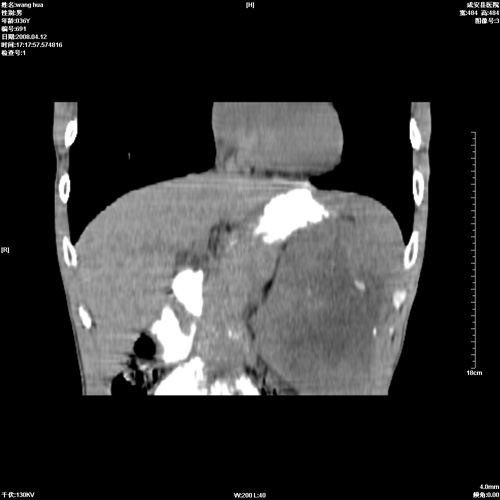

标题: CT12809:男36岁,自感上腹胀5天,B超诊断为脾肾之间占位,血 [打印本页]

标题: CT12809:男36岁,自感上腹胀5天,B超诊断为脾肾之间占位,血

请各位老师先分析一下定位 明天做增强

确实需要强化!先大胆预测一下,来源于脾脏的占位,血管瘤或淋巴瘤可能性大。

脾脏肿瘤,有钙化,增强再说

脾脏明显增大,其内见巨大低密度灶,境界不清,病史较短,考虑恶性病变脾血管内皮细胞肉瘤可能。建议增强扫描与脾脏淋巴瘤及血管瘤鉴别。